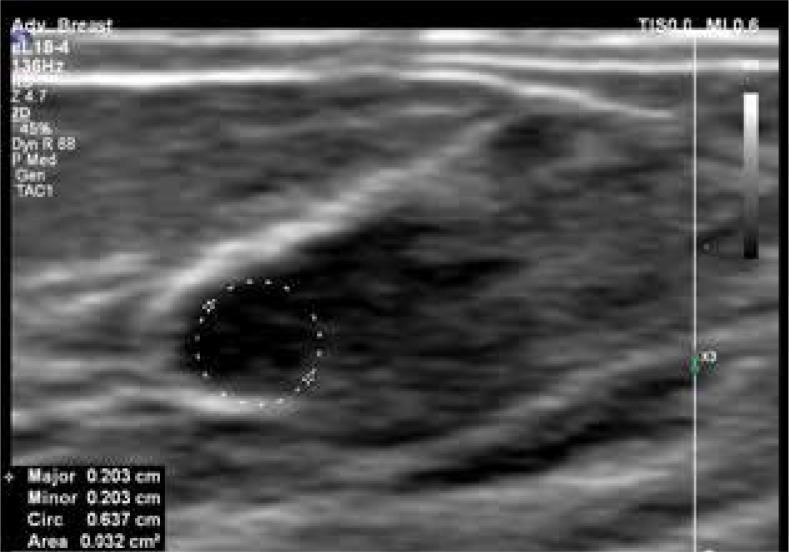

The intricate development and physiological dynamics of the mammary glands, orchestrated by a delicate interplay of hormones, are crucial for reproductive function and lactation. Beginning with intrauterine clusters evolving into mature glands, hormonal fluctuations throughout puberty and the menstrual cycle finely tune mammary tissue growth. Oestrogens stimulate the proliferation of epithelial cells, while progesterone orchestrates the formation of lactiferous glands. During pregnancy, oestrogen and progesterone induces hyperplasia of lobules and ducts, preparing the breast for lactation. Prolactin is vital for lactation and stimulates milk production during pregnancy and postpartum. As shown by ultrasonography, physiological changes during lactation reflect glandular tissue transformation for milk secretion. Clinical and physiological changes, including increased blood flow, contribute to mammary growth and firmness, complicating clinical examination. Ultrasonographic findings reveal variability in women's glandular and fat tissue distribution, suggesting that milk production is not solely determined by anatomical factors. Though not directly linked to milk production, blood flow dynamics hint at a threshold for optimal lactation. Understanding these complex hormonal and physiological mechanisms is crucial for comprehending mammary development, function, and clinical assessment.